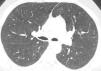

Centrilobular ground-glass nodules were found to be more prominent in the upper lobes of the lungs in thorax computed tomography (CT) (Figure 1a). Abdominal CT and ultrasonography were found to be normal. Endoscopic biopsy for stomach pain was reported as eosinophilic gastritis. Eosinophilic infiltration was observed on transbronchial lung biopsy. Numerous eosinophilic granulocytes (40%) were observed in bone marrow biopsy without increased blast cells. A prominent mast cell population was not observed. There was no malignant infiltration. FIPLI-PDGFRα mutation, JAK-2 mutation and Philadelphia chromosome were also found to be negative.

Figure 1a. Axial CT image at lung window setting showing centrilobular ground-glass nodules (circles).